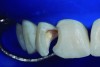

The partial pulpotomy was performed for tooth No. 7 due to the pulp exposure during the caries removal procedures (Figure 5). The superficial contaminated pulp tissue was removed with a No. 1012 spherical diamond bur at high speed with water cooling to allow a better reparative response. This procedure was limited to removal of the infected dentin and damaged pulp tissue, removing the injured odontoblast cell layer. During this step, the remaining pulp tissue was analyzed and found to have good consistency and abundant red bleeding (Figure 6). After the pulpotomy, a solution of calcium hydroxide was used for irrigation along with a sterile cotton pellet to achieve hemostasis and disinfection. After hemostasis, the tooth was treated with direct pulp capping: the exposed area was covered with calcium hydroxide powder (Figure 7) and calcium hydroxide cement (Figure 8). The cavity was provisionally restored with the use of a restorative GIC (Figure 9).

Fig 5. Partial pulpotomy with No. 1012 diamond bur under water cooling.

Figure 5

Fig 6. Aspect of the pulp after partial pulpotomy, showing the abundant red bleeding.

Figure 6